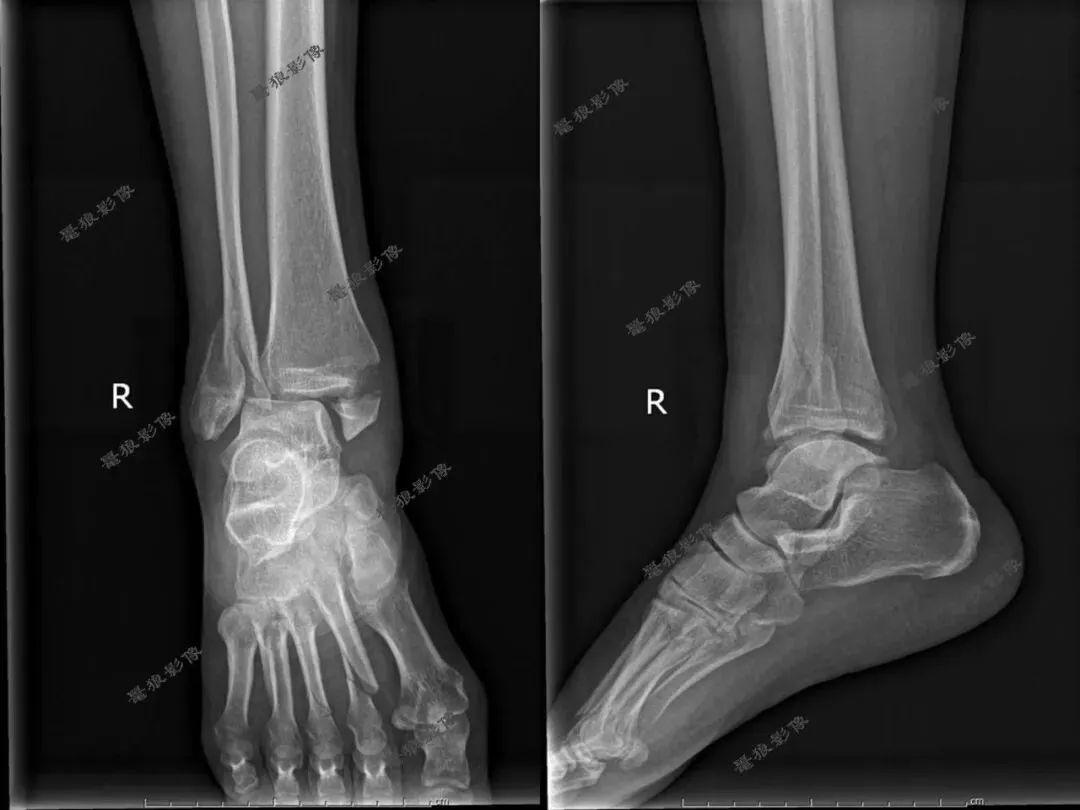

F,62y。跌伤左踝部肿痛活动受限3小时余。

术前CT:

1、左三踝粉碎性骨折,胫距关节半脱位,踝关节软组织肿胀;

2、左足舟状骨、内侧楔骨、第1-4跖骨近端骨折。

术后X线:

1、左三踝骨折内固定术后;

2、考虑左足第3、4跖骨基底部骨折可能;

请结合临床及术前CT。